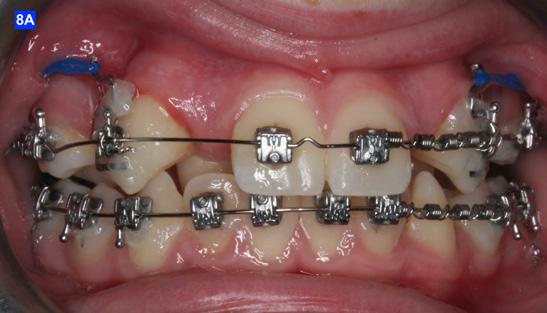

Finally, after 21 months of treatment, the patient and the parents consented to the odontectomy of the maxillary first bicuspids. The informed consent forms for the extractions and placement of TADs were signed by the parent, and all questions were answered. Risks, benefits, alternatives, and the result of no treatment at all were reviewed. Immediately after the odontectomy of #14(5) and #24(12), 1.6 x 8.0 mm AnchorPro (OrthoOrganizers) TADs were placed just mesially to the maxillary second bicuspids.6 In office power arms (a .018 x.025 SS) were fabricated and bonded to the buccal surface of the maxillary cuspids, just above the bracket.7 The purpose of the power arm is to place the applied force as close to the center of resistance of the tooth as possible. In this manner the line of action (power hook to the TAD) is parallel to the occlusal plane. The source of the force is an EC, and it must be replaced at least bi-weekly. Both arches had a .018 SS arch wire. There was a small off-center bend (tip-back, gable bend) “V” pointing occlusally, mesial to the maxillary second bicuspids.8 The purpose of this bend is to keep the roots parallel during the translation of the cuspids. There was a small OCS between #21(9) and #23(11) to shift the maxillary midline to the right. Another OCS was placed between #32(23) and #34(21) to facilitate the alignment of the mandibular left cuspid (Figure 8-A, B, C, D).

Figure 8A: TADs in situ, frontal view 8B: TAD in situ, right lateral view 8C: TAD in situ, left lateral view 8D: Power arms Figure 9A: Maxilla, occlusal view 9B: Maxilla, occlusal view 9C: Maxilla, occlusal view Figure 9D: After the removal of the Hyrax, occlusal view Figure 10A: Center bend “V” pointing gingivally Figure 10B: OCS between the cuspids and the central incisors Figure 10C: Composite build-ups on the mandibular first molars Figure 10D: Adrian “U” bend spring